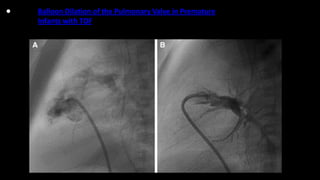

• Balloon Dilation of the Pulmonary Valve in Premature

Infants with TOF

3. Balloon dilatation of the RVOT and pulmonary valve, although not widely

practiced, has been attempted to delay repair for several months.

•